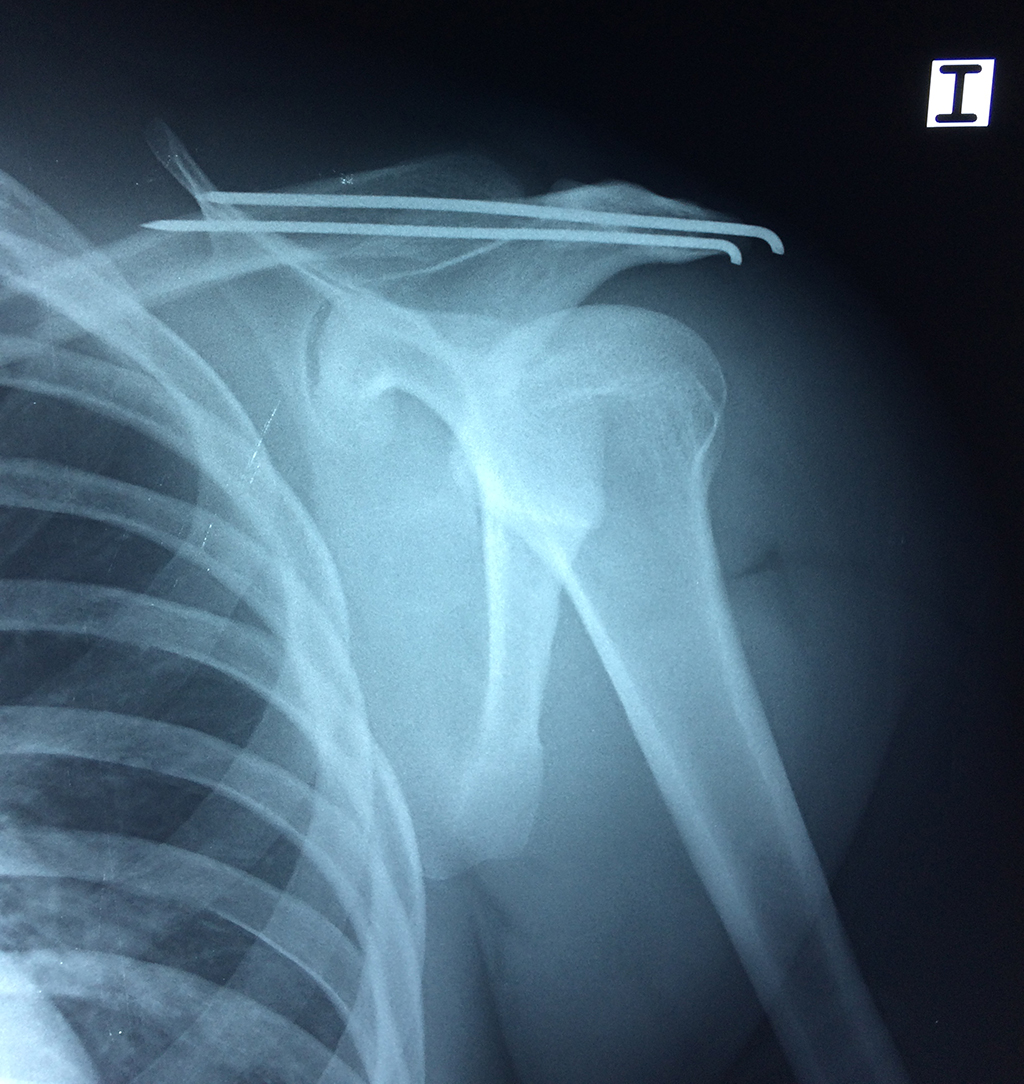

La principal articulación del hombro es la que une la cabeza del húmero con la escápula, recibe el nombre de articulación escapulohumeral y presenta dos superficies articulares, una de ellas corresponde a la cabeza del humero que tiene forma semiesférica y la otra es la cavidad glenoidea de la escápula, estas superficies están recubiertos por cartílago que permiten un movimiento suave e indoloro.

Exteriormente una envoltura de tejido blando circunda el conjunto, es la llamada cápsula articular que está reforzada por varios ligamentos que le dan estabilidad e impiden que los huesos se desplacen más allá de sus límites fisiológicos. Un conjunto de músculos y sus tendones se unen a las superficies de los huesos y hacen posible la movilidad de la articulación, entre ellos es muy importante el manguito rotador formado por cuatro músculos que proporcionan movilidad y estabilidad al hombro.